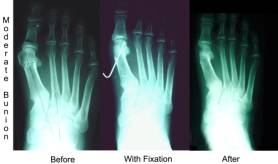

Evaluation of the bunion is essential to the proper surgical approach. The most important consideration is the angle between the first and second metatarsal.This is called the IM angle.This stands for the inter-metatarsal angle. The picture on the right shows that angle. We have three different surgical approaches based on this angle. Of course the structure of the rest of your foot also adds to our decision. If your IM angle is 0-10 degrees we call this a simple bunion. We can just remove the bunion bump and do some soft tissue work around the bunion. Usually you can walk on this the same day as the surgery.

If your IM angle measures 11-14 degrees we call this a moderate bunion. If you just take off the bump as a simple bunion then the chances of the bunion reoccurring increases. We want to try to decrease this angle. We try to move the metatarsal head closer to the second metatarsal. This effectively reduces the IM angle by up to 4 degrees. There are sometimes additional corrections needed to straighten the big toe. By moving the head of the metatarsal over in a moderate bunion the recurrence rate goes down drastically. Usually this requires you not to walk on the foot for a period of 10-21 days.